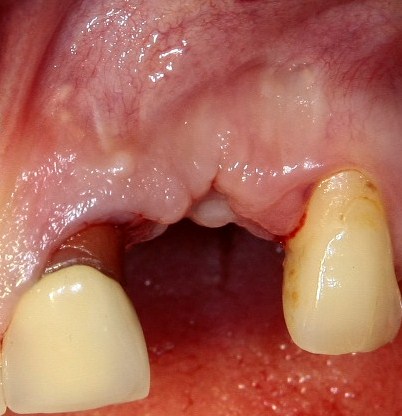

Прошло 3 месяца. Послеоперационная рана выглядит следующим образом:

Мы можем приступить к имплантации.

Делаем разрез, скелетируем костную ткань: